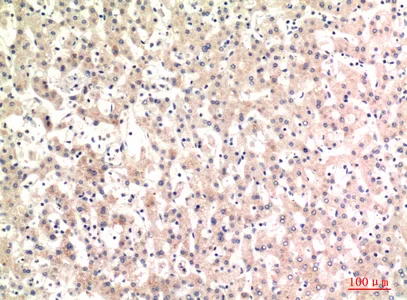

alpha 1 Fetoprotein Rabbit Polyclonal Antibody

Cat: APRab00486

Size1:50μl Price1:$150

Size2:100μl Price2:$280

Size3:500μl Price3:$1200

Size2:100μl Price2:$280

Size3:500μl Price3:$1200